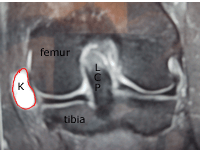

Coupe horizontale IRM

Parfois le kyste peut se développer et se faufiler entre les tissus sous la peau ou sur le côté du genou (exemple de l'image IRM).